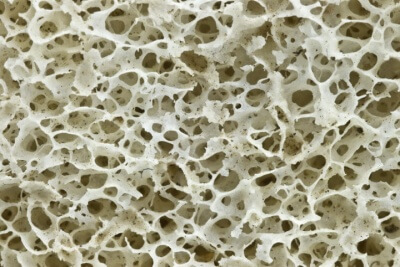

Биокомпозиционный материал – высокоочищенный костный матрикс, полученный из натуральной кости крупного рогатого скота в результате многоэтапного процесса очистки, химической обработки с соблюдением самых жестких норм безопасности. С сохраненными коллагеновым и минеральным компонентами и природной архитектоникой, в соотношении 25% - коллаген и 75% - минеральный компонент кости, аффинно-связанных костных сГАГ не менее 1,5 мг/см3.

Остекондуктивный и остеоиндуктивный пористый биоматериал для заполнения объема костного

дефекта или полости. Избирательное связывание костными сГАГ тромбоцитов крови (ТК) позволяет создать

химически фиксированную, стабильную концентрацию ТК на материале, немедленно запуская каскад реакций формирования костного матрикса, без дополнительных манипуляций с кровью пациента. Материал характеризуется высокой биосовместимостью с костной тканью. Низкая антигенность, не иммуногенен.